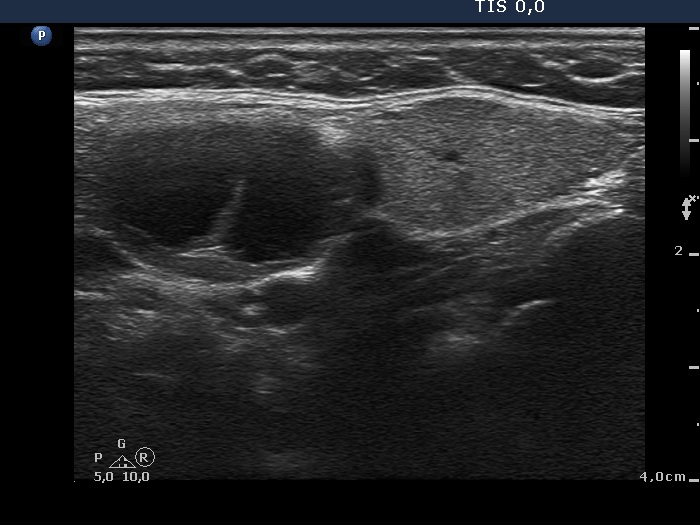

Ultrasonography. The right thyroid was moderately hypoechogenic without any circumscribed lesions. The left thyroid was removed. There were several enlarged lymph nodes in the right submandibular area. The largest one presented two discrete, more hypoechogenic intranodal lesions and a regular hilum.

Comment. This is an unusual case, the nodes (particularly those presented in the video) seem to be benign, reactive-type ones.